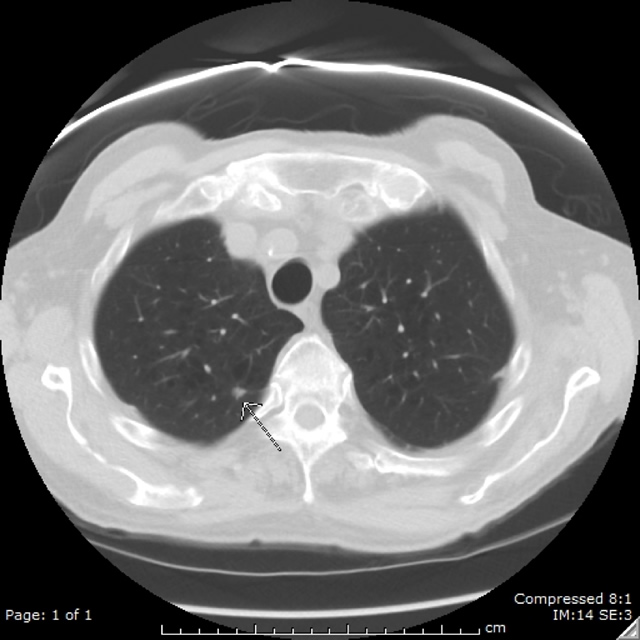

Lung Cancer Screening X Ray

Experience the clarity of Lung Cancer Screening X Ray with our curated collection of comprehensive galleries of images. featuring understated examples of photography, images, and pictures. designed to emphasize clarity and focus. Discover high-resolution Lung Cancer Screening X Ray images optimized for various applications. Suitable for various applications including web design, social media, personal projects, and digital content creation All Lung Cancer Screening X Ray images are available in high resolution with professional-grade quality, optimized for both digital and print applications, and include comprehensive metadata for easy organization and usage. Our Lung Cancer Screening X Ray gallery offers diverse visual resources to bring your ideas to life. Comprehensive tagging systems facilitate quick discovery of relevant Lung Cancer Screening X Ray content. Multiple resolution options ensure optimal performance across different platforms and applications. Time-saving browsing features help users locate ideal Lung Cancer Screening X Ray images quickly. The Lung Cancer Screening X Ray archive serves professionals, educators, and creatives across diverse industries. Instant download capabilities enable immediate access to chosen Lung Cancer Screening X Ray images. Whether for commercial projects or personal use, our Lung Cancer Screening X Ray collection delivers consistent excellence. Professional licensing options accommodate both commercial and educational usage requirements.